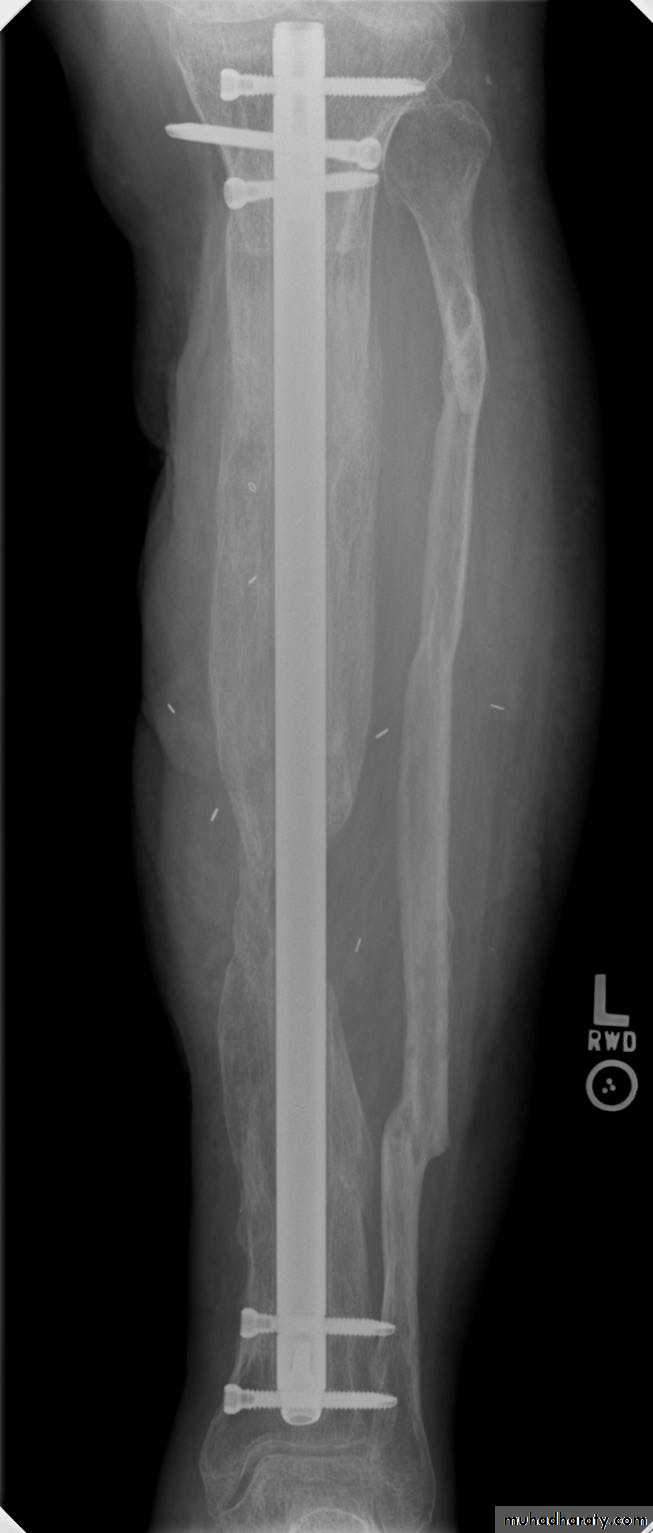

• Treatment: The wound should be left open for inspection and frequent dressing, and then delayed primary closure after few days. The fracture is fixed by external fixator.

• Appropriate antibiotic should be given from the beginning